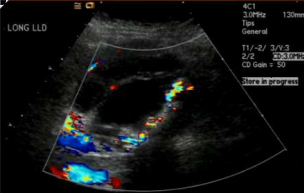

What does this patient have in their gallbladder?

Gallbladder carcinoma, doppler tells you that they are not calcifications, they have vascularity.